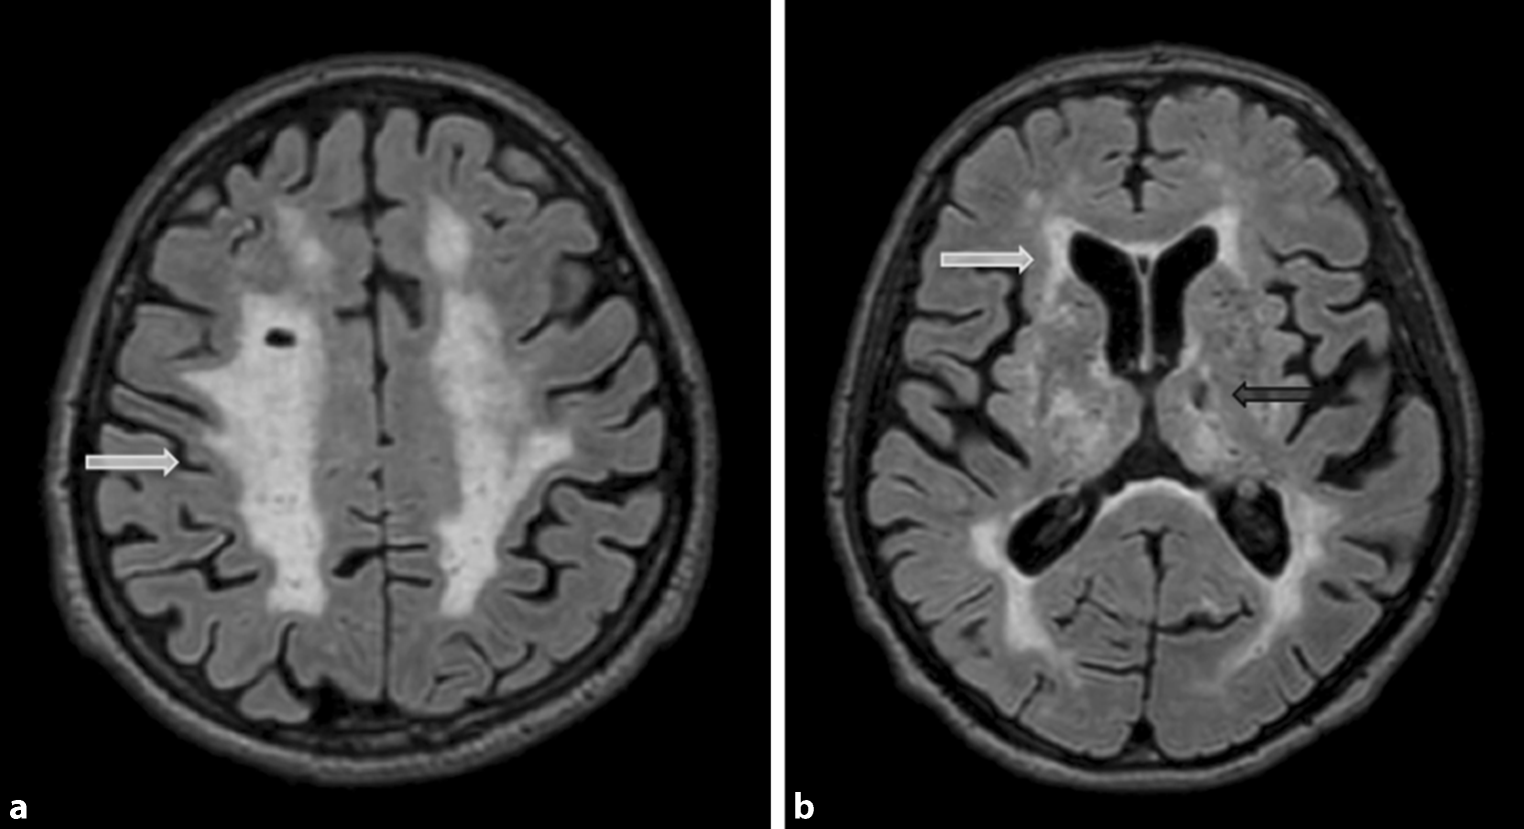

Lacunes and Virchow-Robin spaces

Lacunes are deep, small-vessel infarcts with a CSF-like signal on all MRI sequences (illustrated in Fig. 5). In contrast, Virchow-Robin spaces are enlarged perivascular spaces usually due to volume loss of the surrounding tissue with a predilection for the basal ganglia (illustrated in Fig. 6).

Fig. 5

Lacunes. Illustration of lacunes in the putamen (arrow) on axial Flair images (a) and coronal T2-weighted images (b)